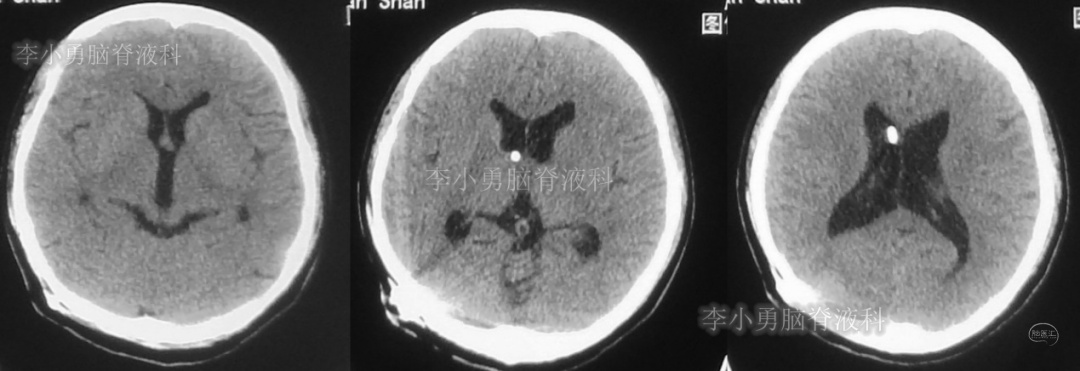

次日,即2018年11月11日,患者第2次到给予脑室腹腔分流术的医院,复查头颅CT(图-5)见脑积水仍严重。

图-5:2018年11月11日头颅CT

但第2次调压后2周,即2018年11月28日,再次到当地的第1家医院复查头颅CT(图-6)见脑积水缓解。

图-6:2018年11月28日头颅CT